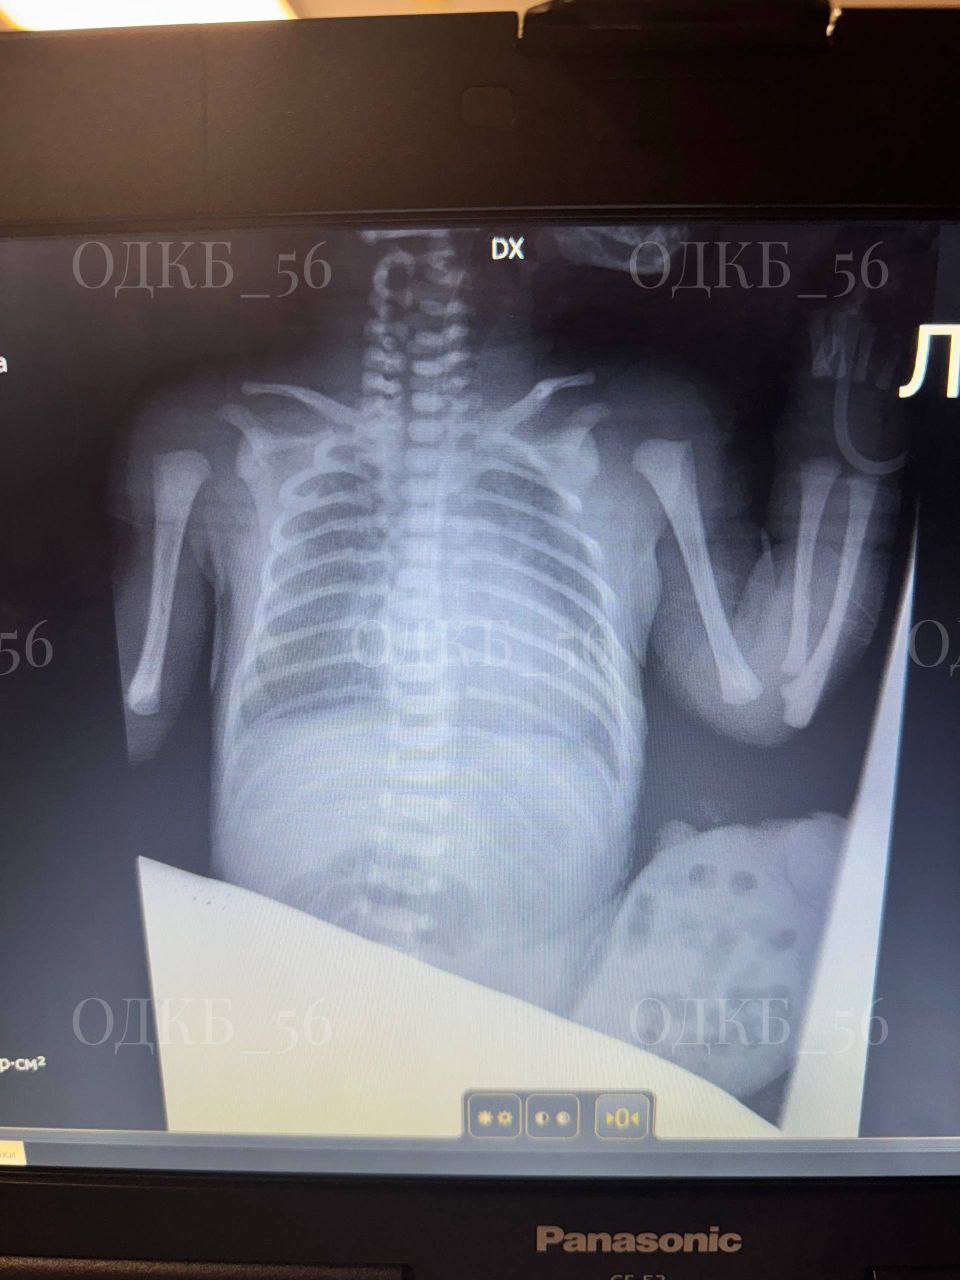

В Оренбурге хирурги спасли новорожденного с редкой патологией

А именно с омфалоцеле больших размеров или грыжей пупочного канатика.

При этом заболевании внутренние органы, чаще всего кишечник и печень, выходят за пределы брюшной полости через пупочное кольцо. Такая патология встречается редко — от одного до пяти случаев на 10 тысяч новорожденных.

Сразу после рождения ребенка доставили из перинатального центра в Областную детскую клиническую больницу. После необходимой подготовки хирурги провели операцию по устранению омфалоцеле и пластике передней брюшной стенки. Органы аккуратно переместили в брюшную полость, а пупок сформировали из кожного лоскута.

Фото: Областная детская клиническая больница